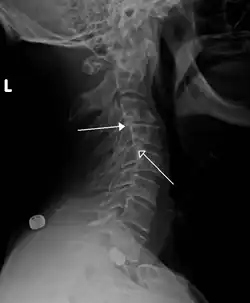

Grade 1 retrolistheses of C3 on C4 and C4 on C5

A retrolisthesis is a posterior displacement of one vertebral body with respect to the subjacent vertebra to a degree less than a luxation (dislocation). Retrolistheses are most easily diagnosed on lateral x-ray views of the spine. Views where care has been taken to expose for a true lateral view without any rotation offer the best diagnostic quality.

Retrolistheses are found most prominently in the cervical spine and lumbar region but can also be seen in the thoracic area.